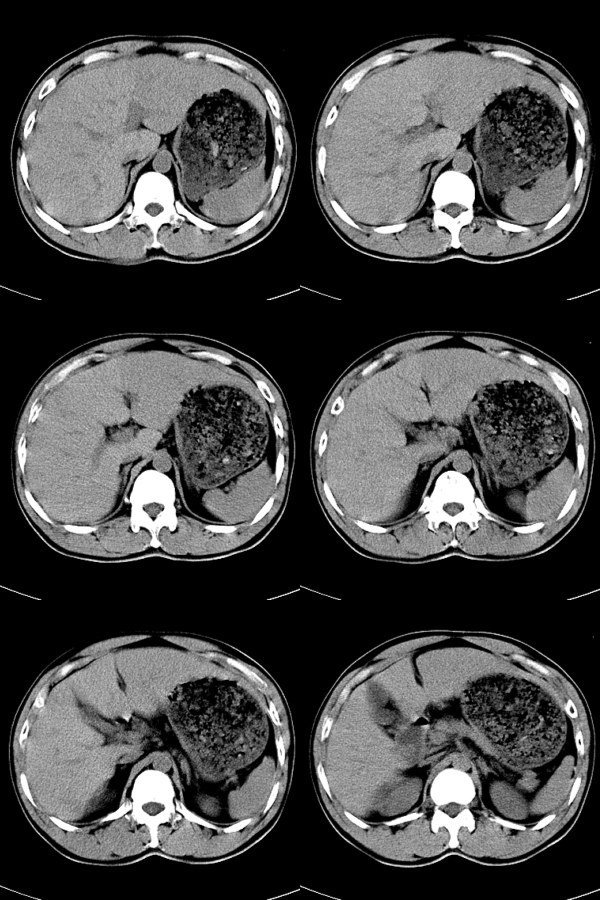

标题: CT17991:M32y,腹部外伤。

32岁男性,外伤后腹部、腰部疼痛。腹部压痛明显,呈“板状腹”。既往体健。

血肿,脾破裂。

考虑脾破裂并腹腔积血。

脾破裂并腹腔积血。

脾破裂并腹腔积血.大网膜血肿或积血